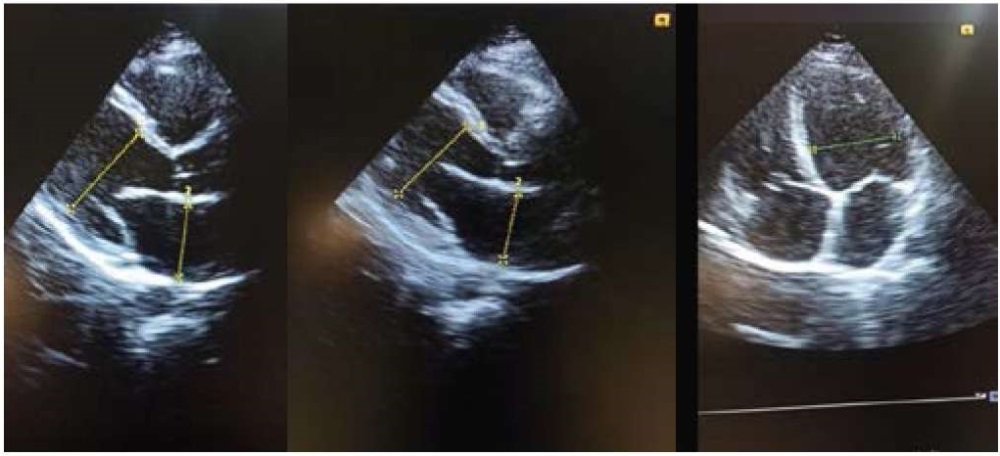

Эхокардиография (07.06.2021). Левое предсердие (ЛП): 50 мм, конечный диастолический размер левого желудочка (КДР ЛД) — 55–56 мм. Фракция выброса (ФВ) ЛЖ — 36–38%. Локальная сократимость миокарда ЛЖ не нарушена. Правые отделы не расширены. Допплерография: митральная (++/+++) (МР) и трикуспидальная (++) (ТР) регургитация. Лёгочная артерия (ЛА): лёгочная гипертензия до 55–60 мм рт. ст. ЭХО-негативное пространство — следы жидкости (2–4 мм за задней створкой ЛЖ). Плевральные полости: с обеих сторон на уровне 7 межреберья жидкость толщиной слоя до 50–60 мм. Заключение: признаки дилатации ЛП, начальной дилатации ЛЖ, значительное снижение глобальной сократимости ЛЖ. Недостаточность МК, ТК, лёгочная гипертензия. Следы жидкости в полости перикарда, двусторонний гидроторакс. На рисунках 8–10 представлены данные эхокардиографии (ЭХОКГ) пациентки.

Рисунок 8–10. Данные эхокардиографии пациентки Т. (07.06.2021)

Figure 8–10. The results of ultrasound research (Echocardiography) of a patient T. (07.06.2021)

ЭХОКГ (21.06.2021): ЛП — 34 мм. КДР — 53 мм. ФВ — 45–47%. ТМЖП — 9–10 мм. ТЗСЛЖ — 9 мм. Зон нарушения локальной сократимости миокарда не выявлено. МР ++. ПЖ — не расширен, ПП — не расширено. ТР +/++. Клапан ЛА — без признаков ЛГ. Плевральные полости — свободной жидкости не определяется. Заключение: умеренное снижение общей сократимости миокарда ЛЖ. Умеренная недостаточность МК.